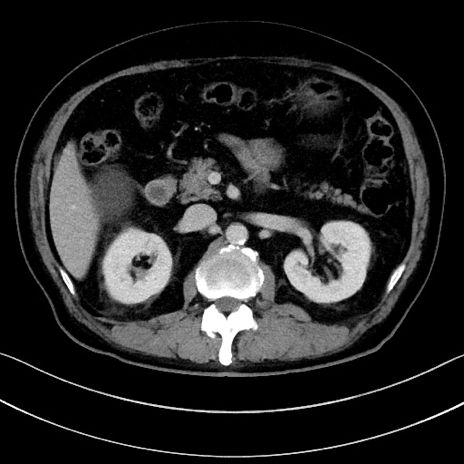

症例15(横断像)

【症例】70歳代男性

【主訴】腹痛

【現病歴】今朝から腹痛あり。全体的に痛い。特に左上の方。排ガスが今日はない。冷や汗が出る。

【既往歴】直腸癌術後

【身体所見】左側腹部〜上腹部に圧痛あり。腹膜刺激症状明らかなではない。軽度反跳痛。左下腹部に術後瘢痕あり。

【データ】WBC 7700、CRP 0.02